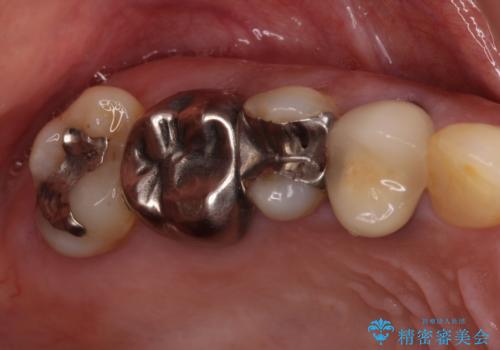

気になる部分を全て治療 総合歯科治療で口腔内環境改善

- 右下の欠損部の治療を希望して来院された患者様です。

部分矯正を行った後にインプラント埋入と手前の歯の根管治療を行い、その後補綴治療を行うこととしました。

治療途中より、上の歯や反対側の銀歯、上顎前歯の色合いや下顎前歯のデコボコが気になってきたため、全てを治療することとしました。